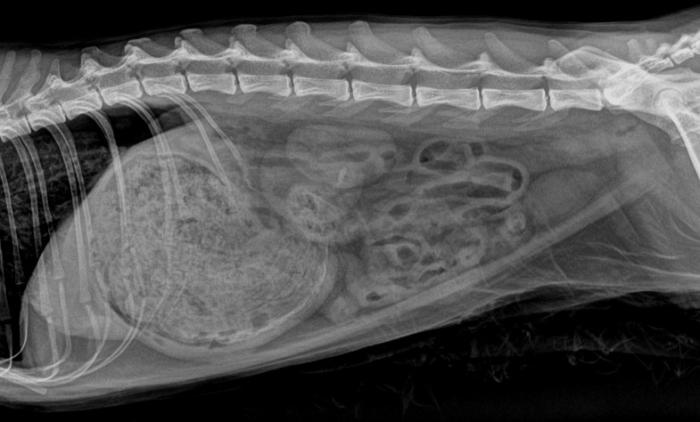

Las radiografías evidenciaron neumotórax en hemitórax izquierdo, fractura múltiple de cadera derecha (isquion-ilion), dilatación gástrica severa con contenido radiopaco, sin pérdida de definición de serosas ni neumoperitoneo (Figura 1). La ecografía FAST mostró discreta cantidad de líquido libre asociado a la vejiga íntegra, posibles coágulos vesicales, estómago distendido con pared hiperecogénica y leve reactividad peritoneal.